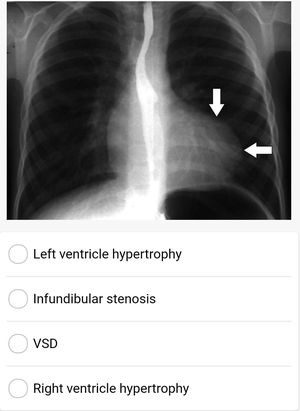

Left ventricle hypertrophy

Lt ventricular hypertrophy

Left ventricular hypertrophy

Rt ventricle hypertrophy ( tetralogy of fallot ) boot shape heart